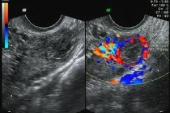

- 一、结果子宫肌瘤挖除术26例,子宫肌瘤挖除及子宫动脉结扎术70例,子宫肌瘤挖除及子宫动脉临时阻断术30例。二、结论子宫肌瘤挖除术患者的手术年龄、体质量指数和子宫肌瘤的数目是术后复发的危险因素,术前产

- 1 结果子宫肌瘤挖除术26例,子宫肌瘤挖除及子宫动脉结扎术70例,子宫肌瘤挖除及子宫动脉临时阻断术30例。2 结论子宫肌瘤挖除术患者的手术年龄、体质量指数和子宫肌瘤的数目是术后复发的危险因素,术前产